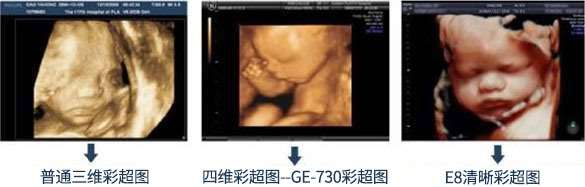

三维彩超VS超声影像(四维彩超)

三维彩超 超声影像(四维彩超)

画质 某个时间点上的静态图片,画质清晰 画质高清,动态活动图像

3.技术设备 武汉百佳妇产医院引进多台美国GE超声筛查设备,筛查、成像一步到位。在360°立体观察宫内胎儿发育情况筛查的同时,还能清晰显示胎儿在宫内的动态。